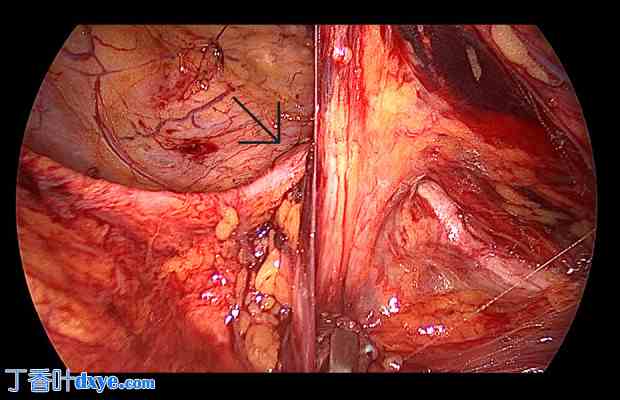

两周后,患者接受了择期手术。再次入院时,患者情况良好,肾功能指标正常。手术时,患者取仰卧位,在脐旁做切口后,插入一个10mm套管针。另在右侧(10mm套管针)和左侧(5mm套管针)旁正中放置两个操作孔。术中插入导尿管,并用生理盐水部分充盈膀胱。第一步是从髂前上棘至腹壁下动脉切开腹膜。腹腔镜下追踪输尿管,从髂动脉向下追踪至其疝入闭孔处(图2)。精确分离右侧输尿管,直至将其从闭孔疝中释放出来。接下来,仔细追踪输尿管至膀胱三角区。输尿管松解术后,盆腔内有足够的脂肪组织保护输尿管,防止其粘连和与网片直接接触。此外,术中意外发现股疝(图 3)。最终,植入一块 ProGrip Mesh®(10×15 cm),其位置比腹股沟疝修补术中通常放置的位置更靠尾侧;因此,它覆盖了闭孔疝和股疝(图 4)。由于该自粘网片的钩子朝向腹侧疝侧,因此无需额外固定。随后,使用 Polysorb 3/0 单向连续可吸收缝线缝合腹膜,以防止与肠道粘连。

图 2.

右侧输尿管(黑色箭头)疝入闭孔管。